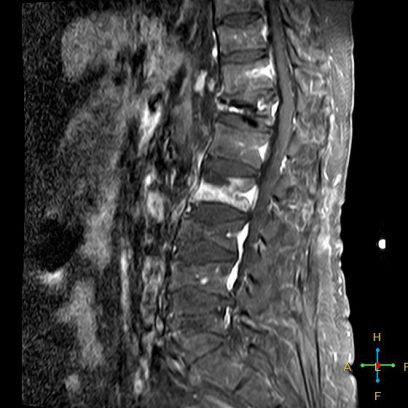

——良性压缩性骨折MR信号特点—— 良性骨折的修复过程:缺血性变化--修复(骨髓水肿、血流增加或充血现象)--修复近完成(血流恢复正常)--慢性期(脂肪组织再生)。 正常成人:椎体为黄骨髓,T1WI 、T2WI 均为高信号。 当骨髓内出现水肿时,T1 低信号, 与残余的正常骨髓形成明显对比,所以椎体压缩骨折后,MR 信号改变以 T1WI 上观察最好;而在常规 T2WI 图像上,病变骨髓的长 T2 高信号与正常骨髓脂肪信号差别较小,不易观察;T2WI 脂肪抑制技术对于突出显示骨折区长 T2 组织信号具有独特优势,对于判断椎体是否发生脂肪变及骨折是否愈合也有一定价值。 急性早期,椎体压缩,局部缺血,骨髓水肿,T1WI 不均匀低信号,T2WI 高信号,增强扫描无明显的强化。 随后,骨折部位开始修复,血流量增加,增强扫描可出现明显的强化,平扫信号无改变。 慢性期,骨髓内脂肪组织再生,T1WI 椎体内呈混杂高信号。

由于大多数外力轻微,椎体内多形成范围局限、移位不明显的骨折线,骨折线周围水肿亦多局限,因此,较少出现全椎体信号异常。

椎体后角回避现象:T1WI 椎体上部或大部呈低信号, 而后角信号不变。

椎弓根改变:由于旋转的扭力或是上下的压力造成椎体血流循环改变而致椎弓根的髓内水肿,使信号改变累及椎弓根,但椎弓根无变形或膨大。

所以,椎弓根的信号改变并非恶性骨肿瘤所特有,约20%~ 30%的良性压缩性骨折会出现椎弓根水肿而信号增高。 恶性压缩性骨折, 约有60%~ 80%出现椎弓根水肿及信号变化,而在椎弓根出现不正常信号的恶性压缩性骨折中, 约有50%~70%出现椎弓根膨大的现象,为其特异性, 可作为鉴别诊断的依据。 椎旁软组织肿块:最典型的表现为椎旁一薄环状异常信号带,因为椎体压缩时常继发椎旁软组织水肿与出血, 这一征象多见于单纯骨折, 病理性骨折少见。